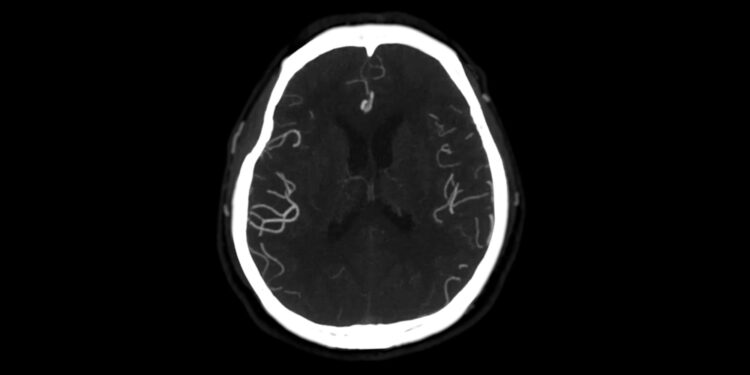

Norint nustatyti šią būklę, atliekamas išsamus fizinis vaiko ištyrimas ir bendra sveikatos būklės apžvalga. Dažniausiai naudojami šie tyrimai:

- Smegenų magnetinio rezonanso tomografija (MRT).

- Elektroencefalograma (EEG).

Tobulėjant vaizdinimo technologijoms, kai kuriais atvejais hemimegalencefaliją galima aptikti dar nėštumo metu, atliekant vaisiaus MRT.

Vaikams, turintiems šį sutrikimą, gali būti ir kitų smegenų sandaros skirtumų. Dažnai pastebimi netaisyklingai išsidėstę neuronai, nevisiškai išsivystęs arba pažeistas jungiamasis audinys tarp pusrutulių (korpusas), ar padidėjusios smegenų skilvelių ertmės. Šie pokyčiai kuria palankias sąlygas dažniems epilepsijos priepuoliams, kuriuos sunku suvaldyti įprastais vaistais. Dėl to kai kuriems vaikams gali prireikti chirurginės gydymo taktikos.